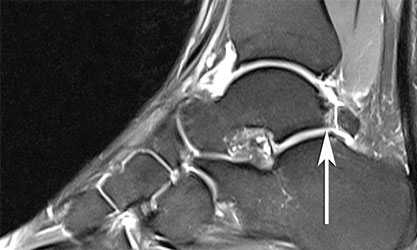

• Магнитно-резонансная томография (МРТ) позволяет увидеть выпот в переднем отделе голеностопного сустава, синовит, а также остеофиты (рис. 1, Б). Может быть видна гипертрофированная связка Бассетта (рис. 1, В)

• В голеностопном суставе могут определяться остеохондральные кисты и хондральные повреждения, свидетельствующие о более выраженных изменениях, ухудшающих долговременный прогноз